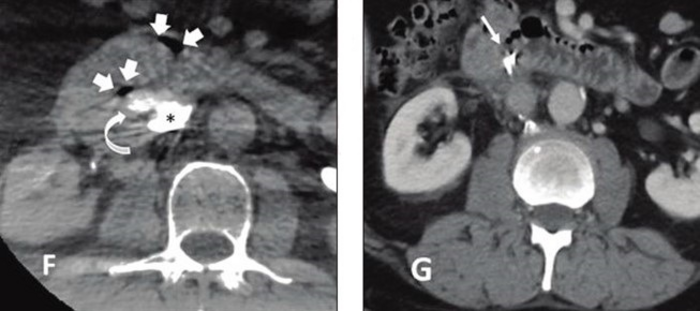

58-year-old patient referred for complex IVC filter retrieval after dwell time of 72 months (IMAGE)

F, Axial image from cone-beam CT immediately following retrieval shows two foci of gas in retroperitoneum (white block arrows) and contained contrast extravasation (curved white arrow) from IVC (asterisk). G, Axial image from contrast-enhanced CT performed 1 day post-retrieval shows interval placement of hemoclips in duodenum (arrow), with no further extravasation evident. This was only patient in study sample who experienced major adverse event during complex retrieval.